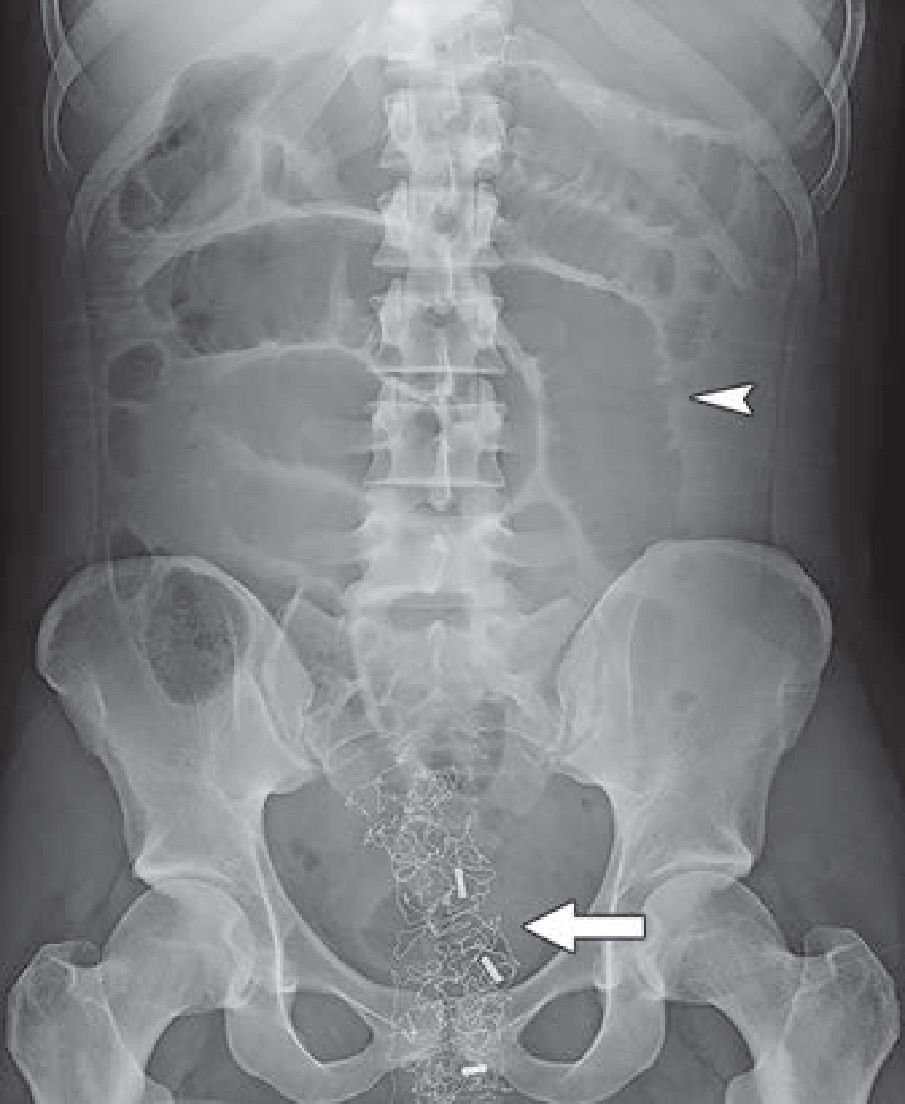

For trans-females, pelvic magnetic resonance imaging (MRI) remains the most reliable modality to evaluate the two most common complications arising from vaginoplasty: hematomas and fluid collection. Cellulitis, abscess, neovaginal prolapse and focal skin necrosis can occur, as well. As Doo cautioned, “At the end of the procedure, radiopaque vaginal packing is inserted, which should not be mistaken for other foreign bodies on postoperative imaging” (Fig. 1). Neovaginal fistulas present less frequently, and for most trans-female patients, these complications may be diagnosed on the basis of clinical symptoms and physical examinations. Although vaginoplasty typically preserves the prostate, it may have atrophied from adjuvant hormonal therapy with estrogen and progesterone, so regular prostate cancer screening guidelines should still be followed.

Fig. 1—Anteroposterior abdominal radiograph shows multiple dilated bowel loops (arrowhead) resulting from adynamic paralytic ileus and radiopaque foreign body (arrow) in pelvis.